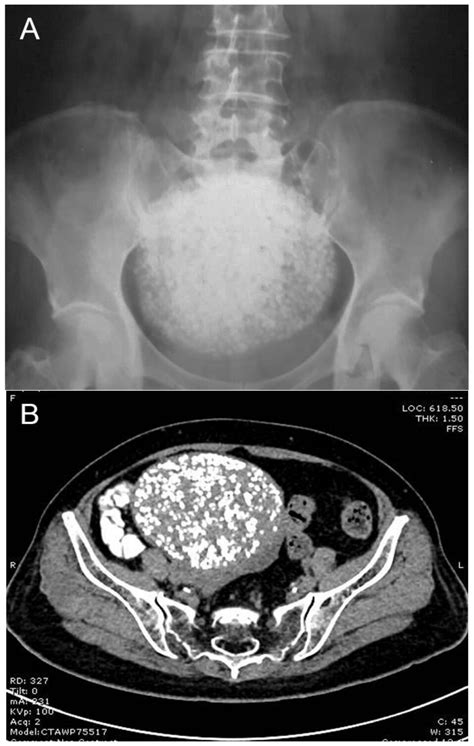

Uterus bubbles symptoms. Calcification is the primary reason for the appearance of ...